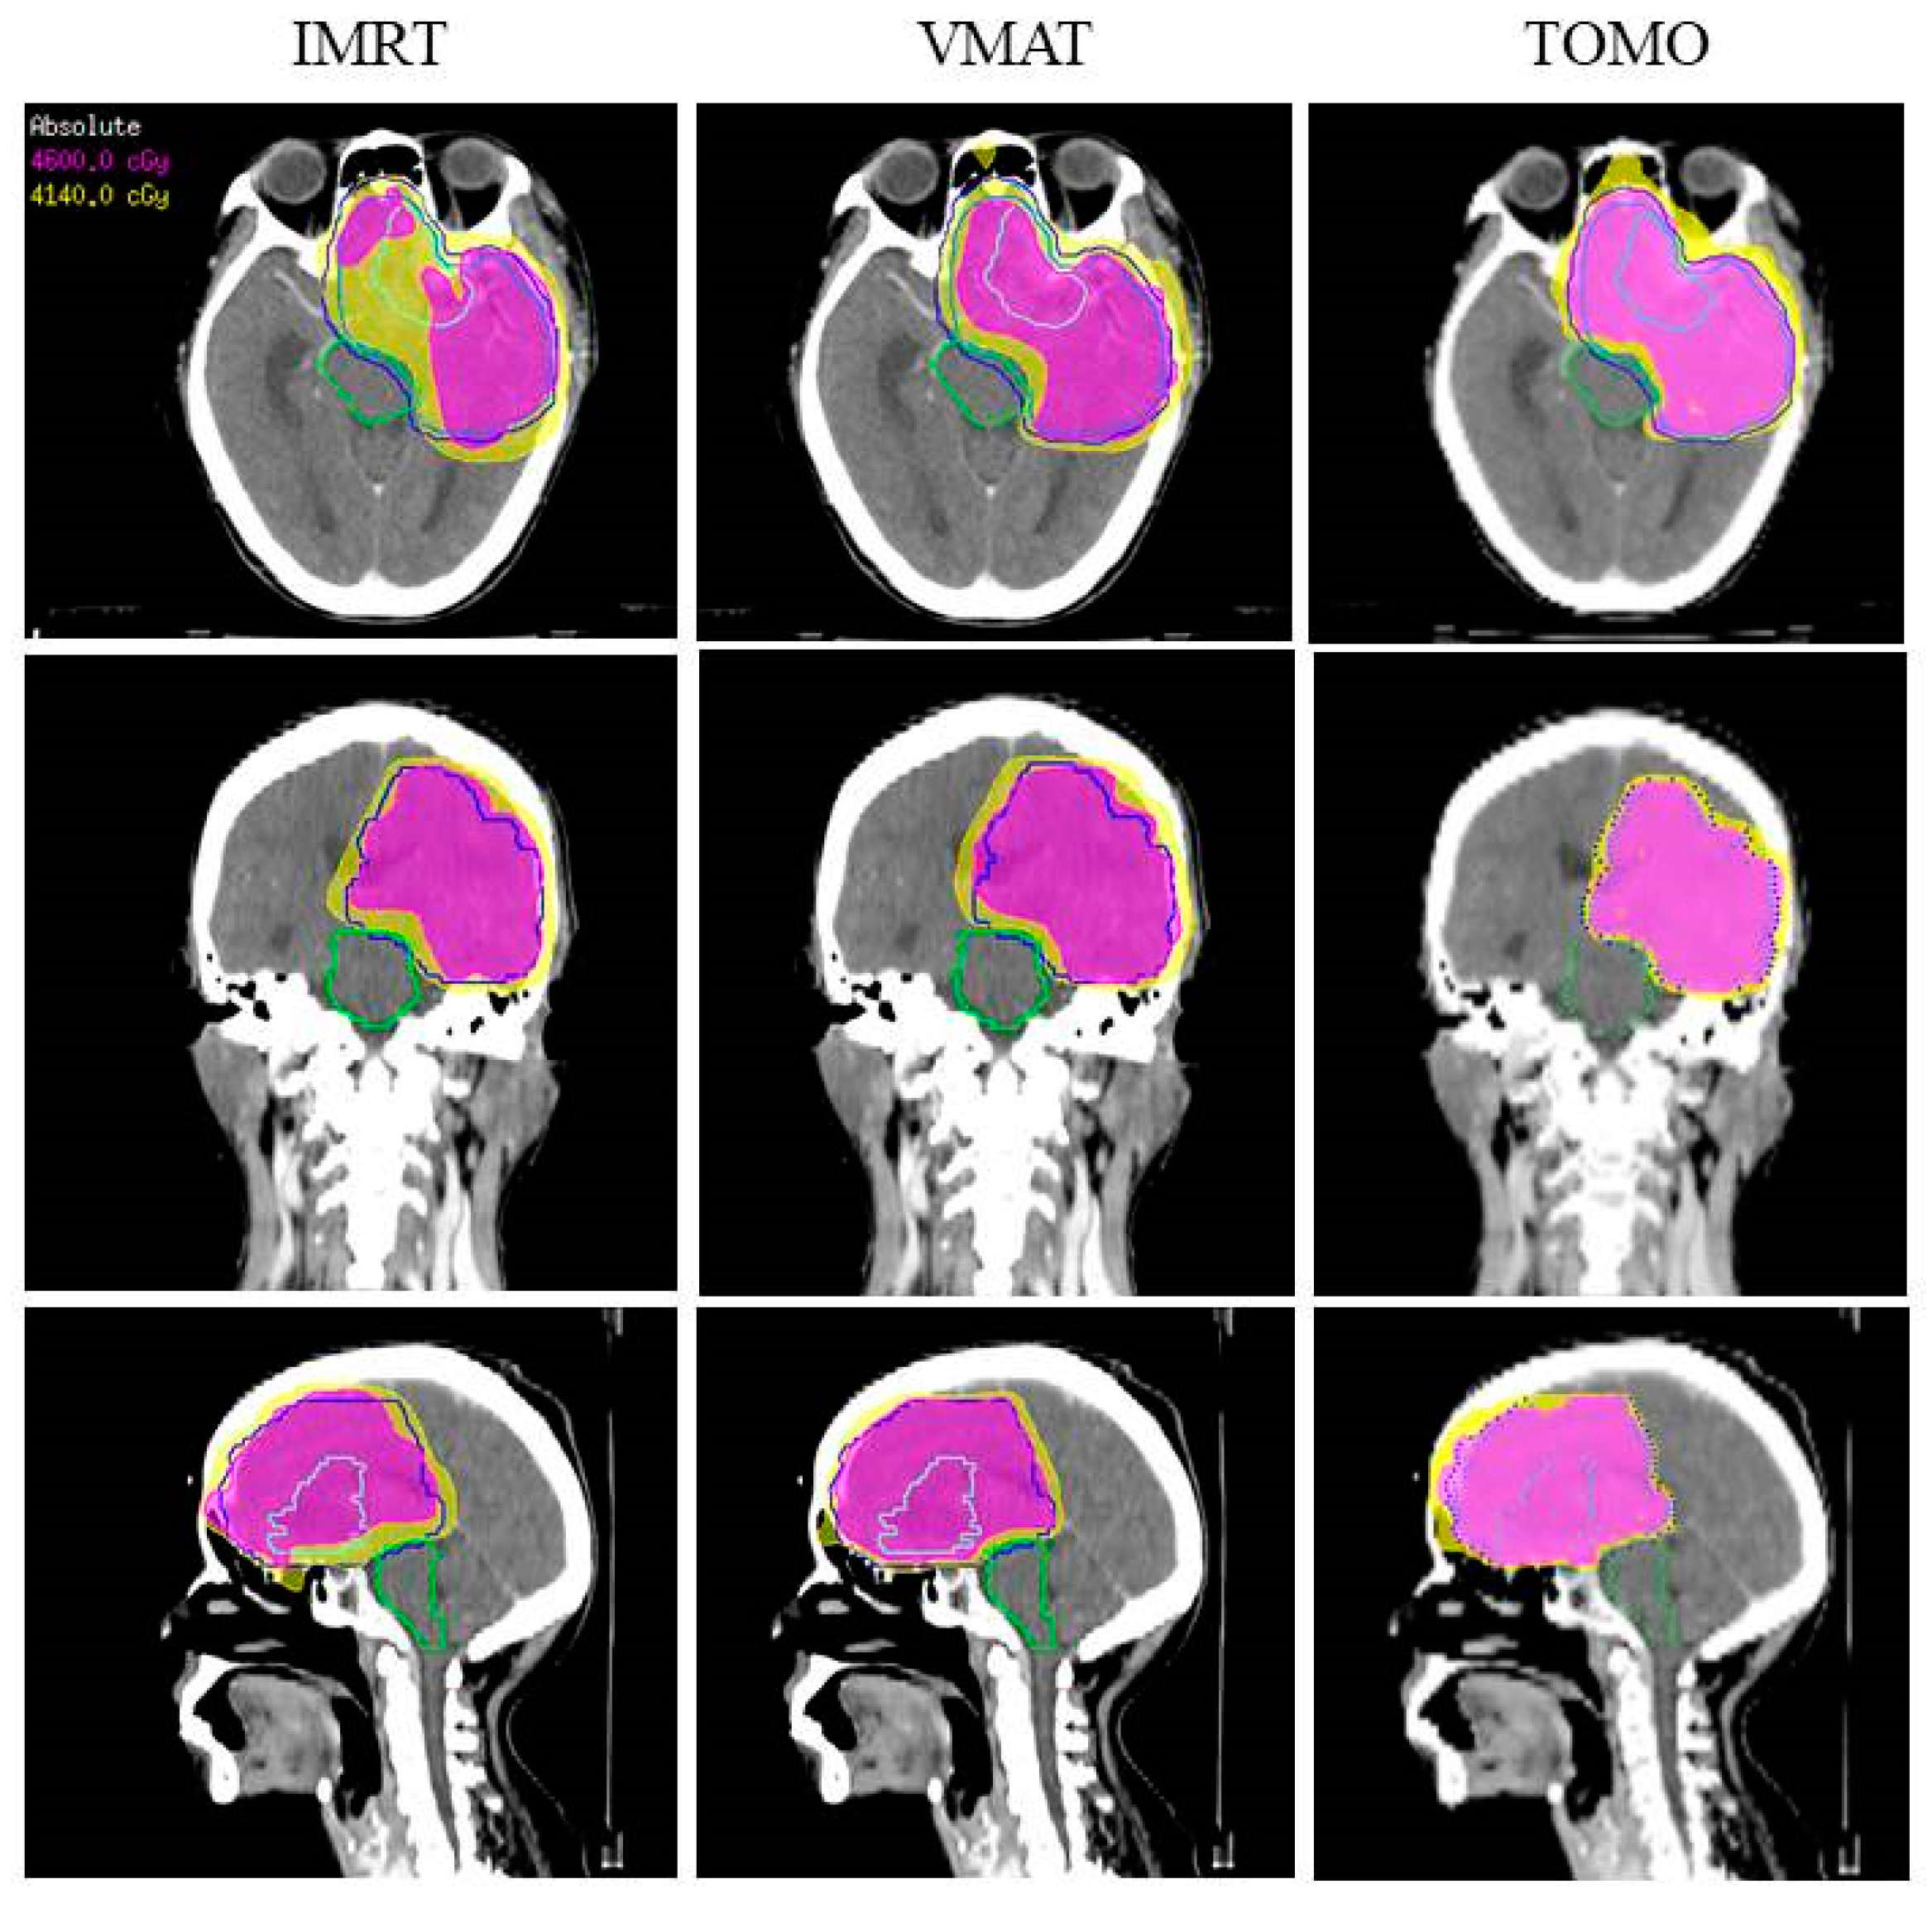

3.2. RT Simulated Planning